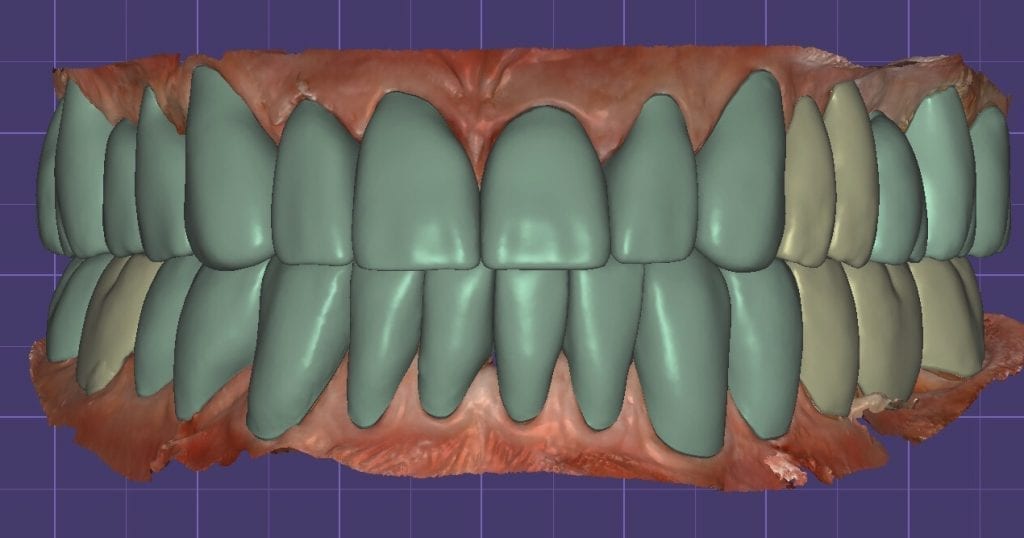

Once the appropriate library is chosen, the digital wax ups are performed. In the subsequent photos you can see the transparent overlay of the wax-ups to the original position of the existing dentition

Once the case is designed to the ideal vertical dimension then multiple shells can be fabricated for treatment. The wax up model can be uniformly reduced by .5mmm’s circumferentially and a temporary shell can be designed. Once the teeth are prepared, these shells can be relined and seated onto the preps.